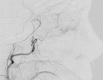

The majority of episodes of spontaneous posterior epistaxis treated with embolisation are idiopathic in nature. The angiographic findings are typically normal. Specific angiographic signs are rare and may include the following: a tumour blush, telangiectasia, aneurysm, and/or extravasation. Selective internal carotid artery (ICA) angiography may show rare causes of epistaxis, such as traumatic or mycotic aneurysms, which require different treatment approaches. Complete bilateral selective external and internal carotid angiograms are essential to evaluation. The images should be analysed for detection of central retinal blush in the external carotid artery (ECA) and anastomoses between the branches of the ECA and ICA. Monocular blindness and stroke are two of the most severe complications. Embolisation aims to decrease flow to the bleeding nasal mucosa while avoiding necrosis of the nasal skin and palate mucosa. Embolisation is routinely performed with a microcatheter positioned in the internal maxillary artery distal to the origin of the meningeal arteries. A guiding catheter should be placed in the proximal portion of the ECA to avoid vasospasm. Embolisation with microparticles is halted when the peripheral branches of the sphenopalatine artery are occluded. The use of coils is not recommended because recurrent epistaxis may occur due to proximal embolization; moreover, the option of repeat distal embolisation is lost. The success rate of embolisation therapy (accounting for late recurrence of bleeding) varies between 71 and 94 %. Results from endoscopic surgery are quite comparable. When epistaxis is refractory to nasal packing or endoscopic surgery, embolisation is the treatment of choice in some centres.